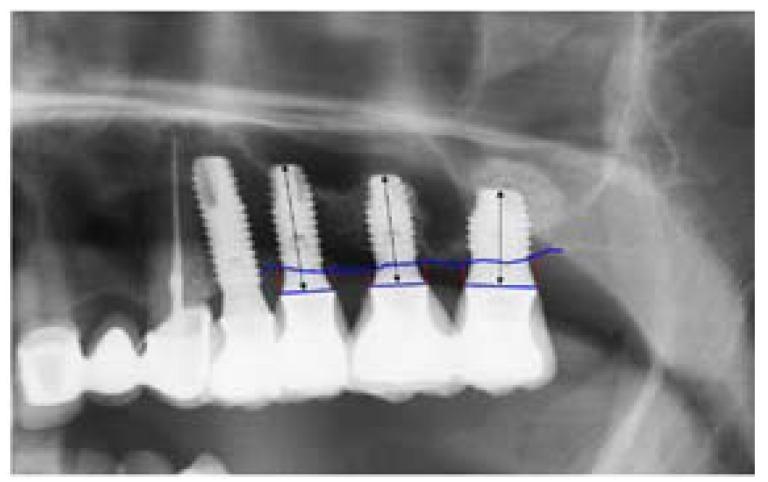

A retrospective study was made of 45 patients requiring maxillary sinus lift or augmentation for implant-prosthetic rehabilitation. Use was made of the handpiece and ostectomy drills for the rotary technique, and of specific tips for ultrasound. The implant success criteria were based on those developed by Buser. The bone gain obtained as a result of sinus lift was calculated from the postoperative panoramic X-rays.

A total of 57 direct elevations of the maxillary sinus were carried out: 32 with the rotary technique and 25 with ultrasound. Perforations of Schneider's membrane with the rotary technique and ultrasound occurred in 7% and 1.7% of the cases, respectively, with membrane integrity being preserved in 91.2%. Of the 100 implants placed, 5 failed after one year of follow-up in the rotary technique group, while one implant failed in the ultrasound group. The rotary technique in turn afforded a bone gain of 5.9 mm, versus 6.7 mm with ultrasound.

回顾性研究了 45 例需要上颌窦提升或增强以进行种植体修复的患者。使用旋转技术的机头和截骨钻,以及超声专用探头。根据 Buser 制定的标准评估种植体成功标准。通过术后全景 X 射线计算上颌窦提升获得的骨增量。

共进行了 57 例直接上颌窦提升术:其中 32 例采用旋转技术,25 例采用超声。旋转技术和超声组的窦膜穿孔发生率分别为 7%和 1.7%,膜完整性保持在 91.2%。在 100 个植入物中,旋转技术组有 5 个在随访 1 年后失败,而超声组有 1 个植入物失败。旋转技术组的骨增量为 5.9mm,而超声组为 6.7mm。